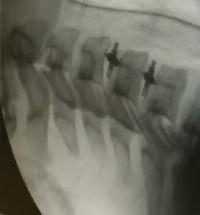

αίματος στα πόδια.

6. Ακατάλληλα υποδήματα Τραυματισμοί λόγω

ΣΥΧΝΑ ΣΥΜΠΤωΜΑΤΑ

• Μούδιασμα, κάψιμο, πόνος ή αίσθημα «μυρμηγκιάσματος» στα πόδια.

και δεν επουλώνονται εύκολα.

• Έλκη στα πόδια ή δάκτυλα

• Αλλαγές στο χρώμα ή τη θερμοκρασία του δέρματος.

• Δυσοσμία ή πύον (σημάδια λοίμωξης)

ΣΟΒΑΡΕΣ ΕΠΙΠλΟΚΕΣ

(οστεομυελίτιδα).

• Νέκρωση ιστών (γάγγραινα)

• Ακρωτηριασμός,

ΑΓΓΕΙΑΚΗ

•

τεχνικές (αγγειοπλαστική, στέντ) ή ανοιχτή χειρουργική (ενδαρτηριεκτομή, bypass) για αποκατάσταση της κυκλοφορίας